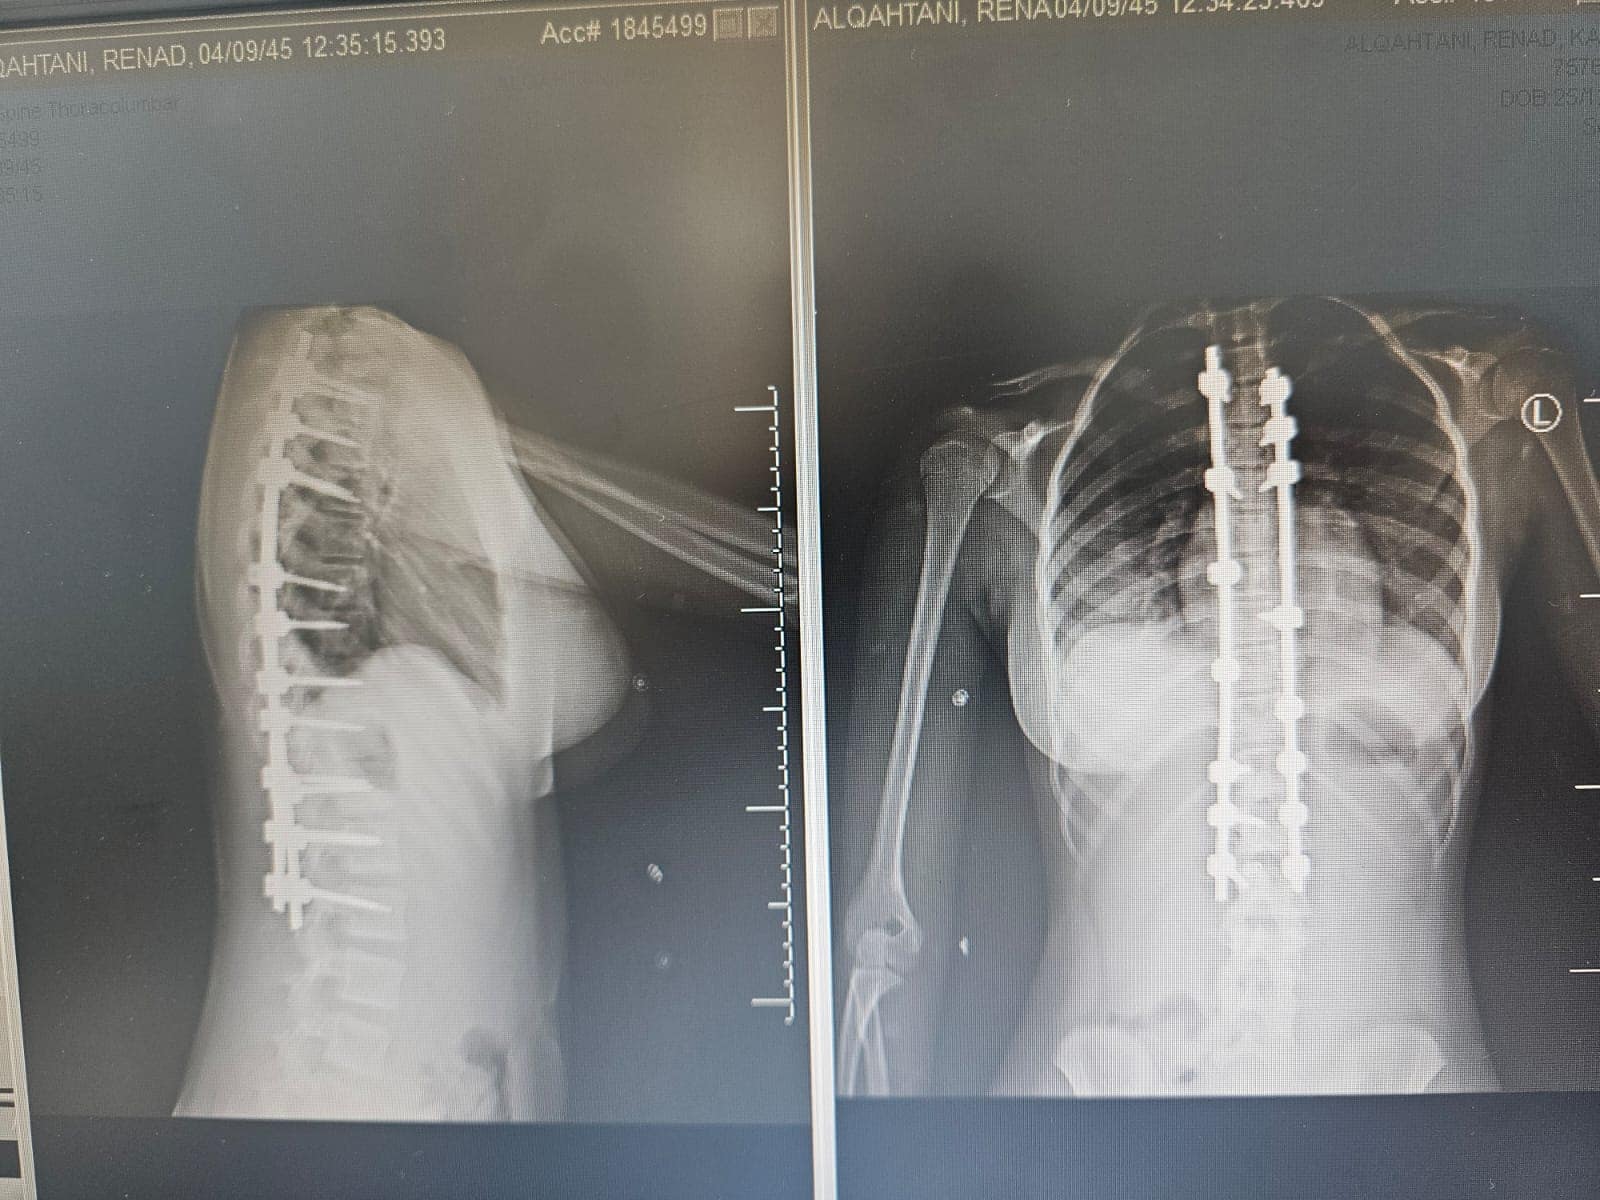

وأوضح تجمع عسير الصحي نطاق بيشة ، أن الطفله حضرت إلى المستشفى وبعد عمل الأشعة والتحاليل اللازمة شٌخصت الحالة على أنها جنف شديد مع وجود صعوبة في أداء وممارسة الأنشطة اليومية ومشكلات في النوم نتيجة إصابتها بانحرافٍ شديدٍ في العمود الفقري (الجنف) منذ الطفوله

وأضاف التجمع : انه وبعد دراسة ملف الطفله قرر الفريق الطبي المعالج ، المكون من الدكتور صالح ال خبتي استشاري جراحة العمود الفقري، والدكتور احمد البنداري أخصائي جراحة العمود الفقري والدكتور اكينبو أخصائي جراحة العمود الفقري، والدكتوره نادر بدوي استشاري تخدير من أجراء عملية التدخل الجراحي لعلاج هذه العيوب والحد من المضاعفات، حيث تمّ إجراء عملية استقامة العمود الفقري بشكل عمودي وتثبيت ودمج الفقرات، بعد ذلك خضعت المريضة لبرنامج علاج طبيعي مكثّف لتقوية عضلات الظهر والفقرات .